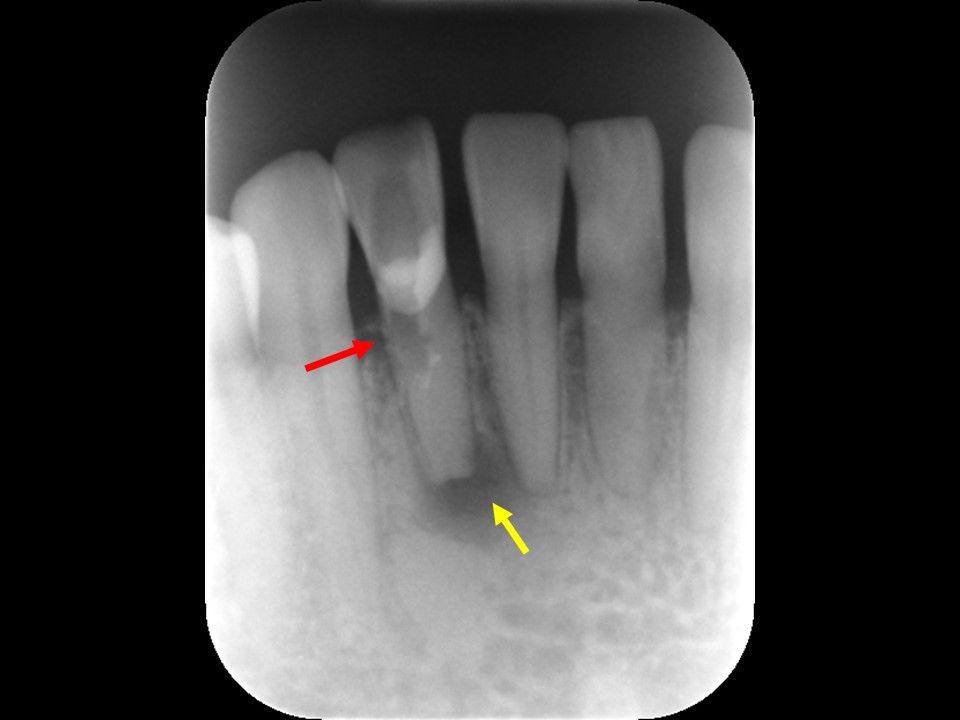

Case2 パーフォレーション(穿孔)

のリペアを行ったケース

診断と治療計画の立案

当該歯のレントゲンおよびCTによる診査にて、根尖部に根尖病巣と思われるX線透過像を認めました。また、歯根の側方には歯の方向を間違えて削った跡があり、パーフォレーション(穿孔、穴)が疑われました(下写真)。

歯髄壊死・歯髄壊疽から生じた慢性化膿性根尖性歯周炎と診断し、感染根管治療を行うことにしました。

パーフォレーションがある場合は、バイオセラミックセメント(MTA,RRMなど)でリペアをする計画としました。

治療前レントゲン | 治療前CT |

---|---|

![]() |

治療前レントゲン |

---|

治療前CT |

術前のレントゲンおよびCT画像です。根尖部に根尖病変と思われるX線透過像を認めます(黄矢印)。歯根の側方には、方向を間違えて削ったと思われる跡が見られます。

根管充填後のレントゲン画像です。パーフォレーション部にバイオセラミックセメントが充填されているのが分かります(赤矢印)。

根管治療7か月後のレントゲン画像です。根尖病変はきれいに治癒し、骨の再生を認めます(黄矢印)。パーフォレーション部も骨吸収は認めず、予後は非常に良好です。